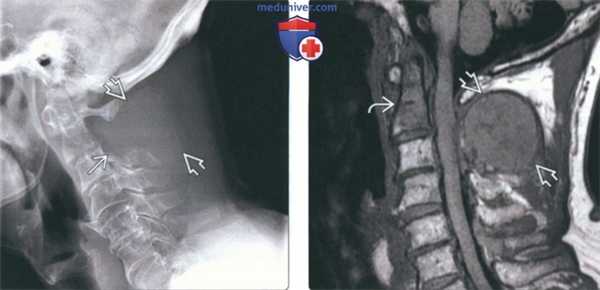

(Слева) На рентгенограмме в бо ковой проекции визуализируется мягкотканная опухоль, замещающая невральную дугу С2. Также определяется деструкция верхнего края боковых масс СЗ. Распространение деструктивных изменений от одной кости к другой нетипично для метастатического поражения.

(Справа) На сагиттальной MPT (Т1 ВИ) у этого же пациента визуализируется крупный очаг в невральной дуге С2. Костный мозг зубовидного отростка замещен опухолью. На рентгенограммах поражение зубовидного отростка выявлено не было - чувствительность МРТ в обнаружении метастазов выше.

(Слева) На рентгенограмме в боковой проекции у пациентки с распространенным бласти -ческим метастатическим поражением на фоне рака молочной железы определяется диффузный склероз шейных позвонков и основания черепа. Видны наложения от сережек.

(Справа) На сагиттальной MPT (Т1 ВИ) определяются множественные остеобластические метастазы с сигналом крайне низкой интенсивности, свидетельствующим о их бластическом характере. Типоинтенсивный сигнал должен сохраняться и во всех стальных последовательностях.